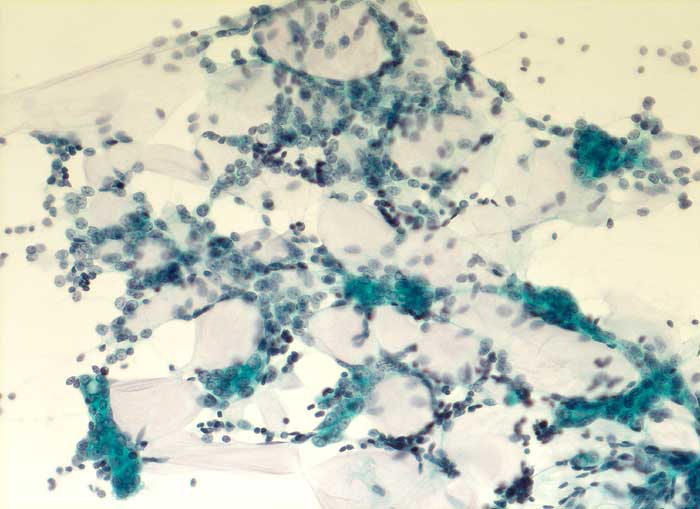

PathoPic – image database / PathoPic ID 5652 - Adenoidzystisches Karzinom

Adenoidzystisches Karzinom

maligner Tumor

Mamma

Zytologische Diagnose: Adenoidzystisches Karzinom.

Kommentar: Adenoidzystische Karzinome kommen vor allem im Bereich der Speicheldrüsen vor, treten aber auch in anderen Organen auf. Sie machen weniger als 0.1% - 0.2% der Mammakarzinome aus.

Zytologie

200

67